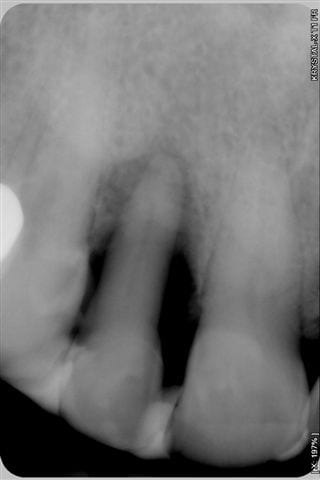

La 5ème radio prise ce jour avec biostimulation en post op, montre que la régénération, que beaucoup d'entre vous pensait impossible, est bien entrain de se faire.

La 3ème radio prise ce jour avec biostimulation en post op, montre que la régénération, que beaucoup d'entre vous pensait impossible, est bien entrain de se faire.

2-Les radio ne semblent pas très standardisées au niveau des contrastes. La 1ere est très foncée, donc le défaut osseux peut sembler plus grave et la 3e est pâle, ce qui montre plus d'os. Ou bien je me trompe...

Net différentiel de contraste et/ou exposition entre la 3ème et les deux premières, non?

première radio le 22/07 et la 3ème aujourd'hui

Je me demandais ce qui pourrait encore vous faire douter, bingo "la première radio est plus sombre que la 3ème" eh bien en voici une prise le 22/7 en urgence et moins sombre, aurez vous encore des doutes quant au bien fondé d'un traitement conservateur laser assisté???